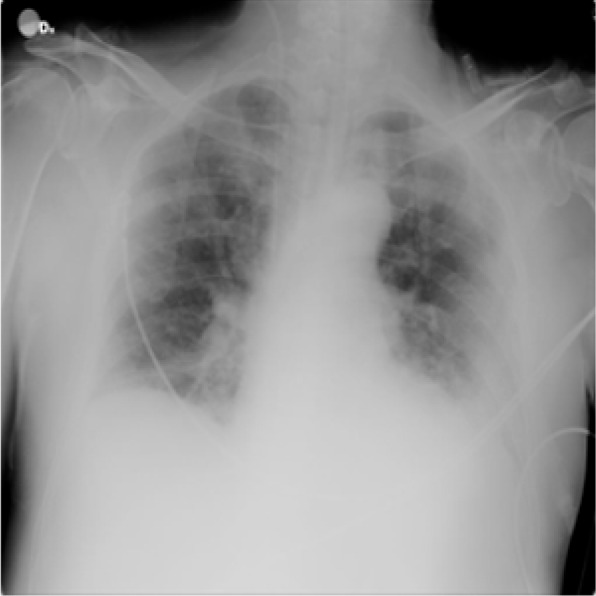

For lung opacity, 6012 CXR images are collected from RSNA CXR dataset (https://www.kaggle.com/c/rsna-pneumonia-detection-challenge/data), while for pneumonia, 1345 images are collected from the Chest X-Ray Images (pneumonia) database (https://www.kaggle.com/paultimothymooney/chest-xray-pneumonia). The sample images are shown in Figs. 2, 3, 4 and 5.

Fig. 2.

Image with class COVID